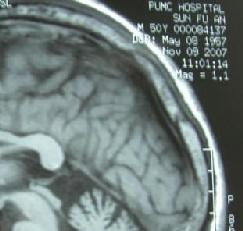

4、CT和MRI顯示額和(或)顳葉不對稱性萎縮。

2、CT和MRI檢查可見特徵性局限性額葉和(或)顳葉萎縮腦回窄腦溝寬及額角呈氣球樣擴大,額極和前顳極皮質變薄,顳角擴大,側裂池增寬,多不對稱少數可對稱,疾病早期即可出現SPECT檢查呈不對稱性額、顳葉血流減少PET顯示不對稱性額顳葉代謝降低,二者較MRI更敏感,有助於早期診斷。目前尚無有效療法主要是對症治療乙醯膽鹼酯酶抑制劑通常無效。對有攻擊行為易激惹和好鬥等行為障礙者,可謹慎地使用小量苯二氮類、選擇性5-HT再攝取抑制劑精神安定劑和普萘洛爾(心得安)等有條件者可住院治療,或由經培訓的照料者給予適當的生活、行為指導及對症處理。